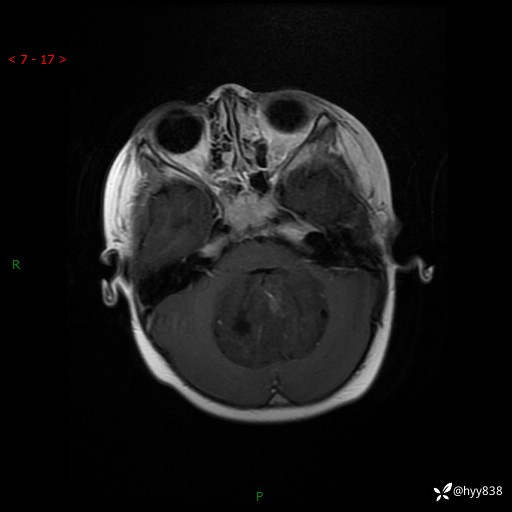

颅脑CT平扫

img